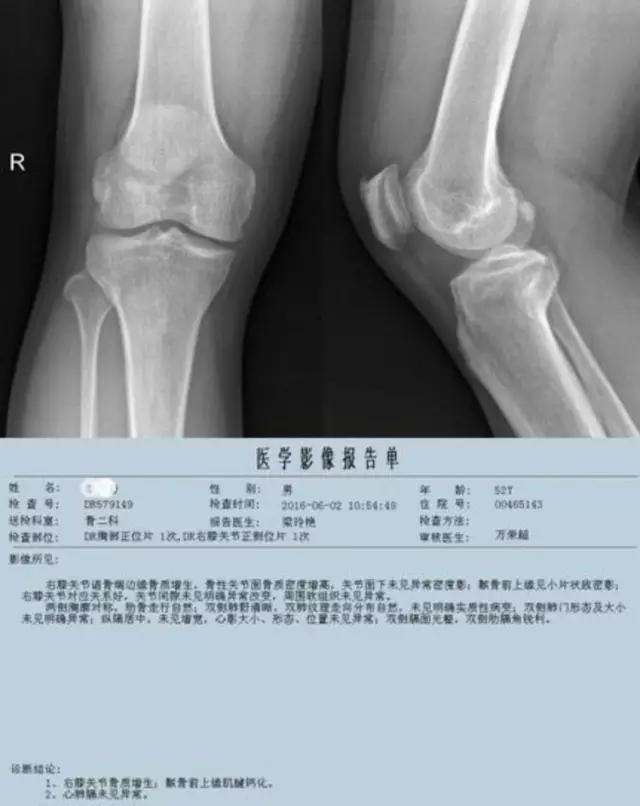

普通X线照片——

只能显示骨的改变,对早期膝关节炎等临床常见疾病的诊断意义不大,但"骨质增生"的诊断报告却常常影响病人一辈子!

膝关节OA是临床常见疾病,不断的磨损会引起一系列的改变,表现在X线照片上会出现以下的四大特征。

利用发病机理——

病例:游XX,男,67岁,右膝肿胀活动困难伴进行性畸形6年。疼痛不重!下图为2010年照片,DR和MR显示胫骨内侧平台骨缺损,无其他病变,很难确诊。

利用疾病发展——

下图为2014年DR,显示关节破坏严重,但疼痛不重,符合神经性关节炎的疾病特点:关节破坏极度严重,临床症状轻微!